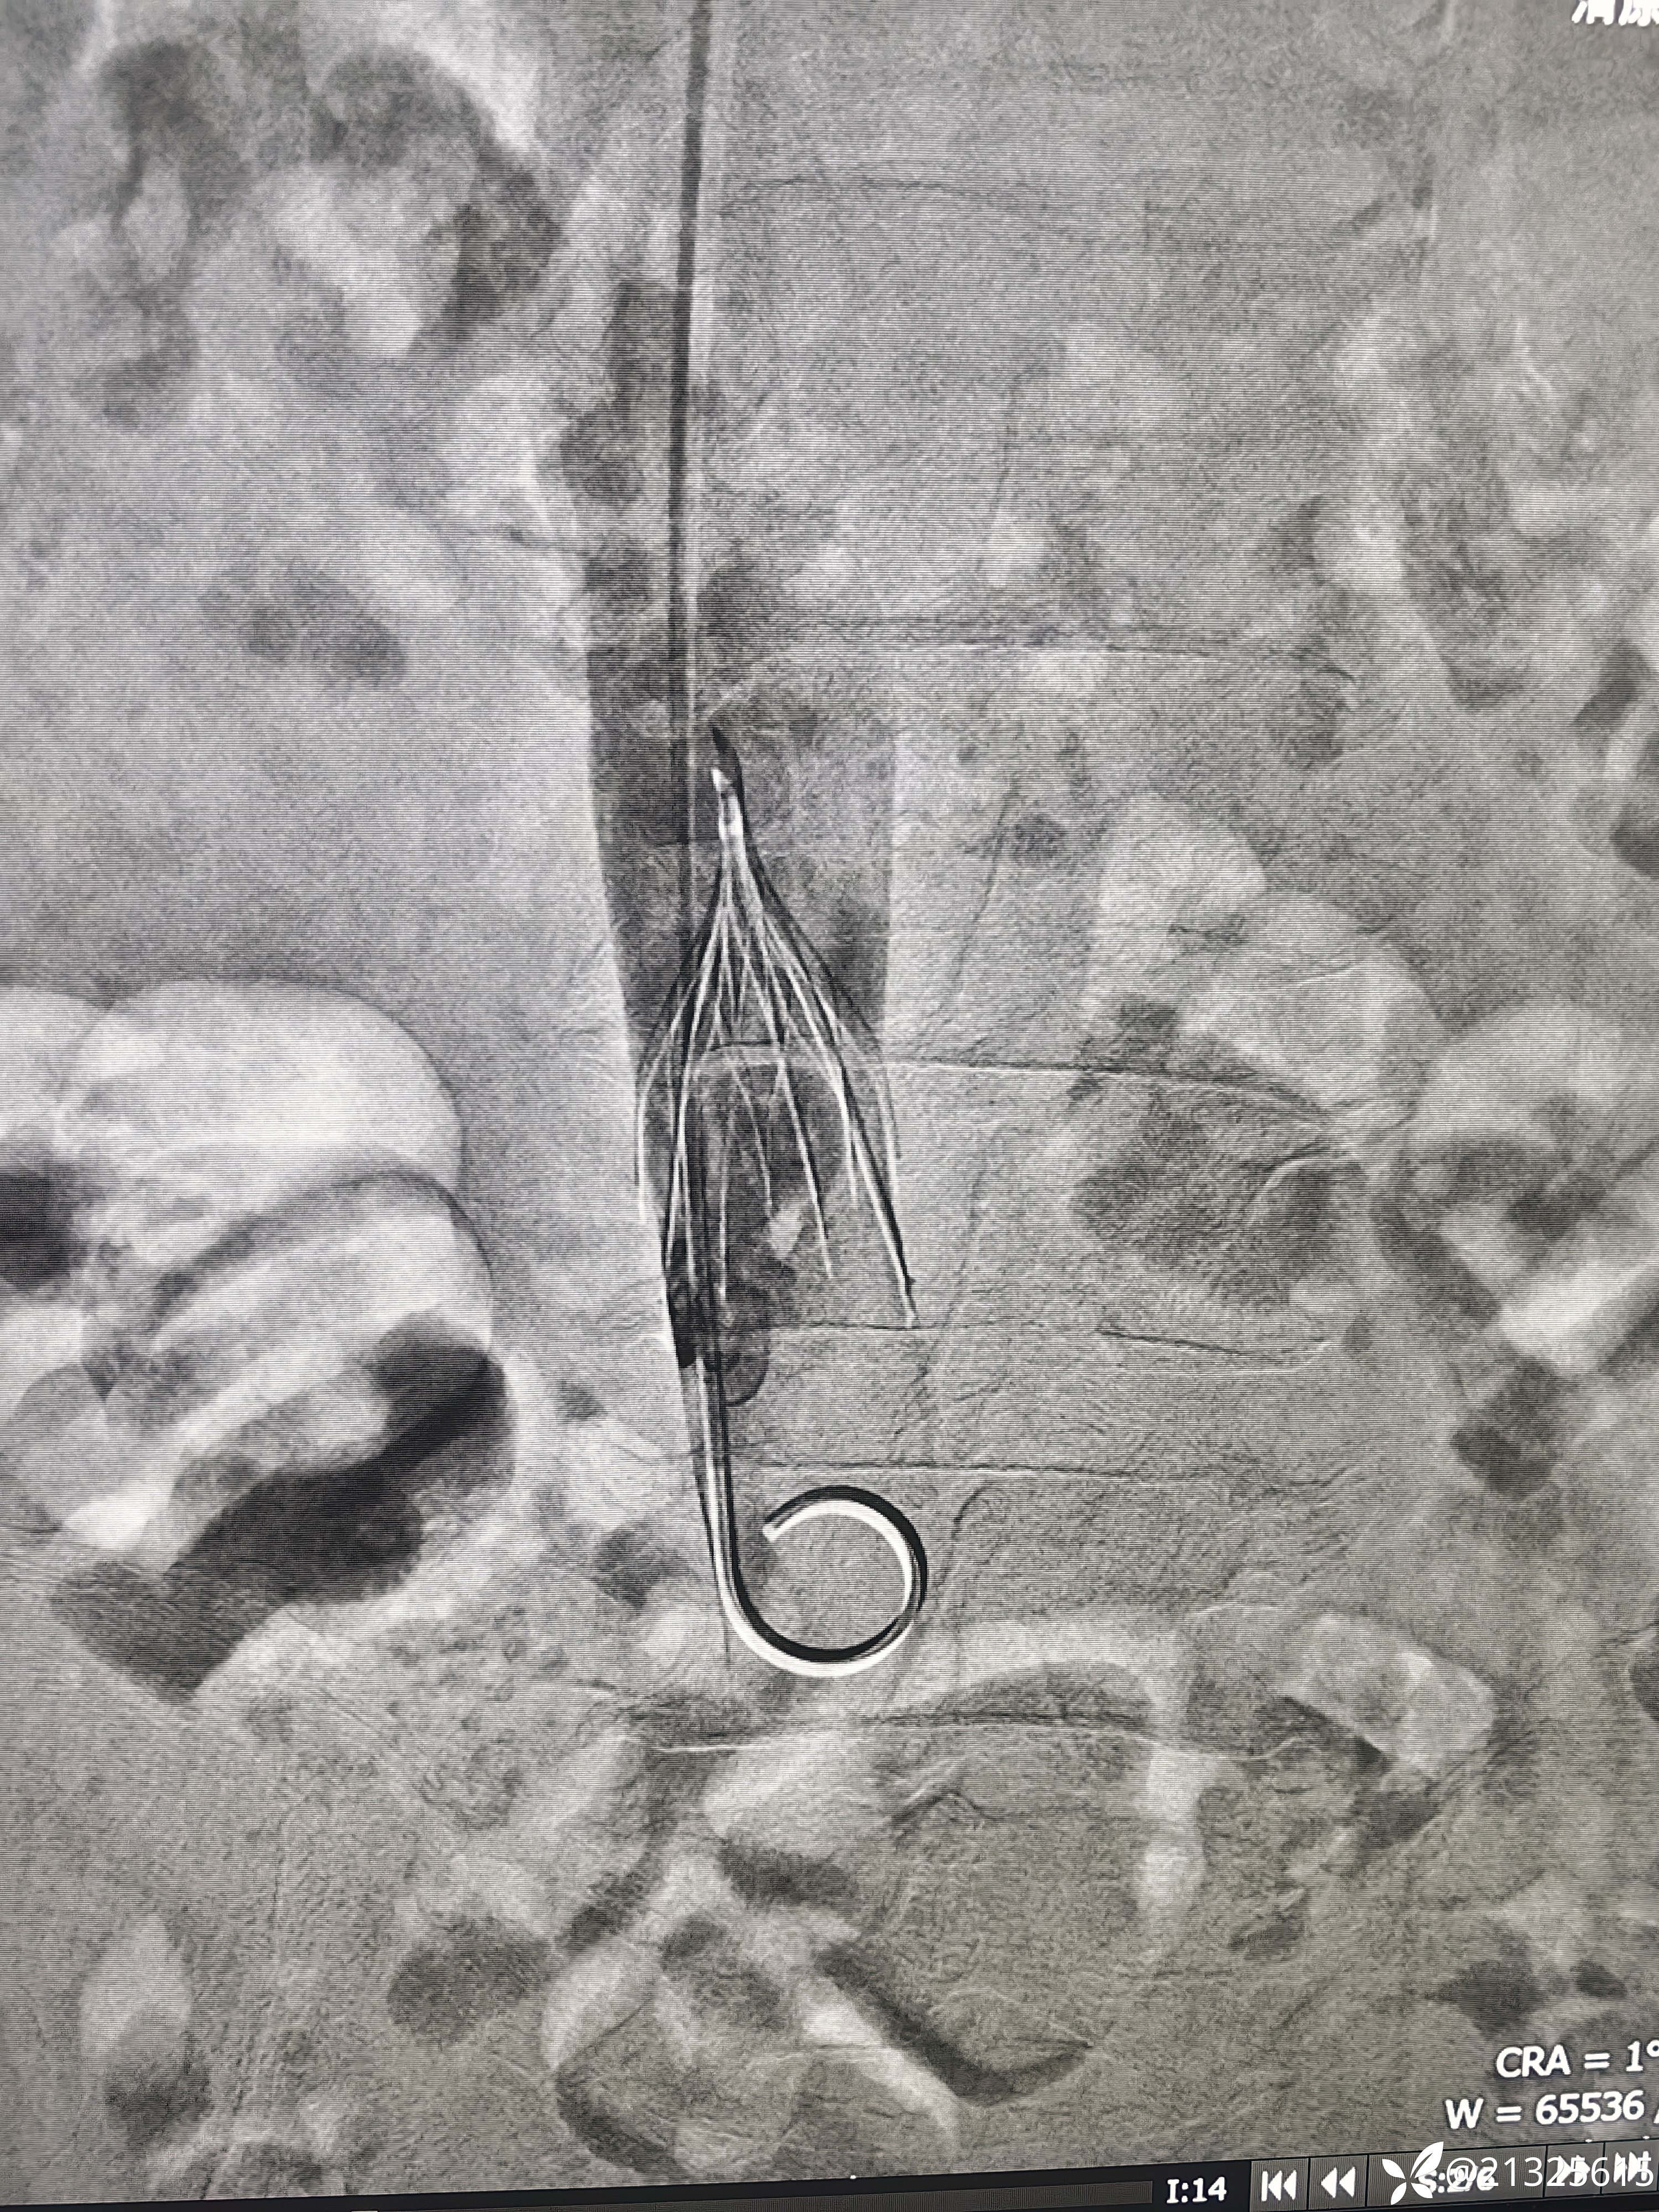

送入取滤器套件,以环状抓捕器套住滤器顶端小钩,

推入外壳将其纳入鞘管取出